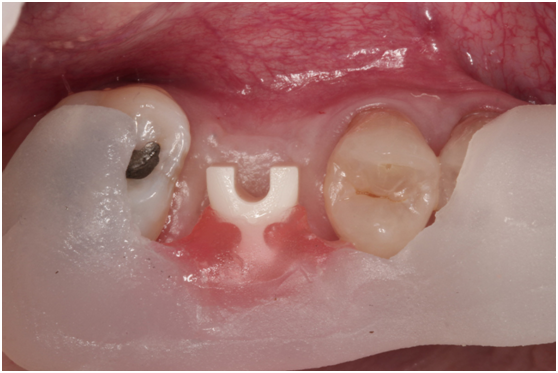

98/01/08經過三個半月做右下第一小臼齒的二階暴露,發覺鄰牙的植體高度竟已掉下來

980305幫患者補角化牙齦並翻開清除發炎組織,期待能阻止繼續骨破壞

期間患者偶爾出血但並無明顯不適